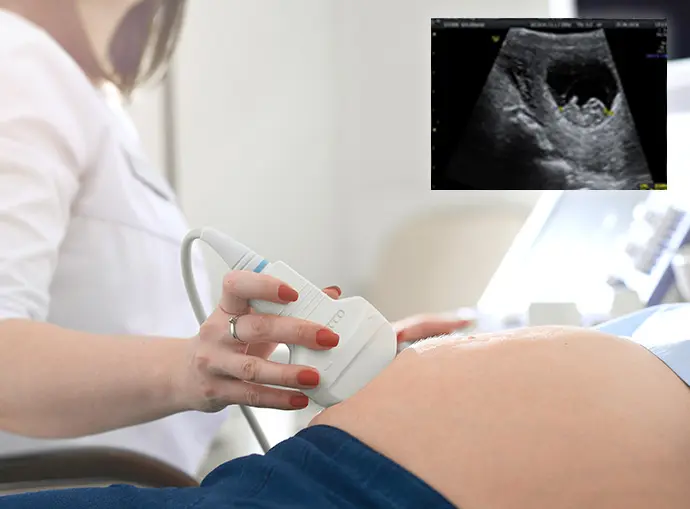

An early pregnancy scan is an ultrasound examination usually performed during the first few weeks of pregnancy, typically between 6 and 10 weeks after the last menstrual period. This scan helps doctors confirm that the pregnancy has started and assess how the embryo is developing inside the uterus.

The ultrasound provides important information about the gestational age, fetal heartbeat, and the overall health of the pregnancy in its early stage. It also helps detect certain conditions such as ectopic pregnancy or multiple pregnancies. Depending on the stage of pregnancy, the scan may be performed through the abdomen or with a transvaginal ultrasound to obtain clearer images.

Before the scan, you may be asked to drink water so that your bladder is full, which helps improve image clarity during an abdominal ultrasound. During the procedure, a trained sonographer uses a device called a transducer that sends sound waves into the body to create images of the uterus and developing embryo.

If clearer images are required in very early pregnancy, a transvaginal ultrasound may be performed. The entire procedure is safe, painless, and usually takes around 15 to 20 minutes to complete.